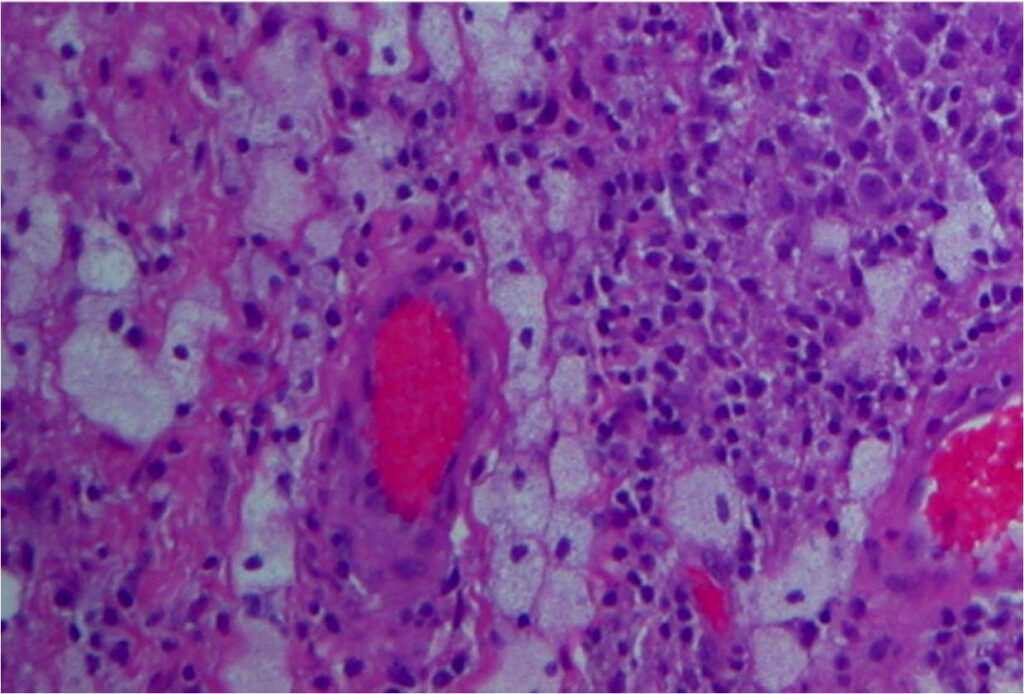

Microscopic

• Dense fibrous tissue divides tumor

• Gives nodular appearance

• Cells

• Small, round to oblong, often reniform or clefted nuclei

• Sometimes prominent nucleoli

• Oblong

• Frequently blend with spindled forms

• Variable numbers of giant cells

• Similar type of nuclei

• Usually contain 8-10 nuclei

• Xanthoma cells

• Sparse mitotic figures

• Low mitotic activity (3 to 5 mitosis x 10 HPF)

• Rarely necrosis is seen

Fig. 7-10: Microscopic pathology. Abundant small hystiocyte-like cells, numerous giant cells and xanthoma cells. In higher magnification images some foamy histiocytes are visible. No mitotic activity is present. Hemosidering deposition is common.